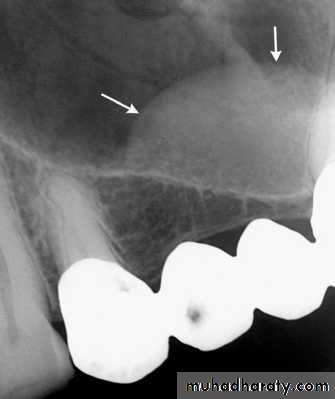

It is important to observe whether the widening is uniform or irregular and whether the lamina dura is still present. For instance, orthodontic movement of teeth results in widening of the periodontal membrane space, but the lamina dura remains intact. Malignant lesions can quickly grow down the ligament space, resulting in an irregular widening and destruction of the lamina duraSurrounding Bone Reaction

The presence of reactive bone at the periphery of a lesion whether corticated or sclerotic usually signifies slow benign growth and ability to stimulate osteoblastic activity in the surrounding bone

Inferior Alveolar Nerve Canal and Mental Foramen

Superior displacement of the inferior alveolar canal is strongly associated with fibrous dysplasia. Widening of the inferior alveolar canal with the maintenance of a cortical boundary may indicate the presence of a benign lesion of vascular or neural origin within the canal. Irregular widening with cortical destruction may indicate the presence of a malignant neoplasm growing down the length of the canal.